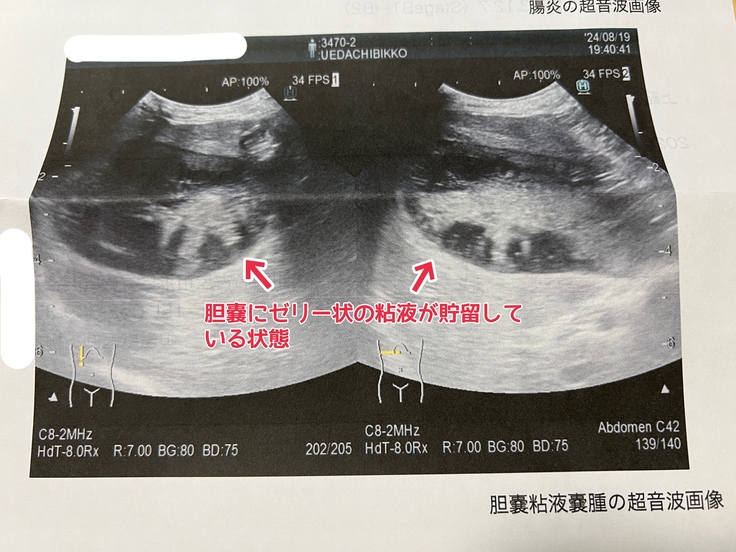

胆嚢粘液嚢腫・・・何らかの原因で胆嚢中にゼリー状の粘液物質が貯留した状態をいいます。胆汁の分泌を障害するために様々な消火器症状を引き起こし、状態が進むと胆嚢破裂に伴う腹膜炎などの重篤な合併症を引き起こします。

↓胆嚢粘液嚢腫 エコー検査画像 2024.8.19.